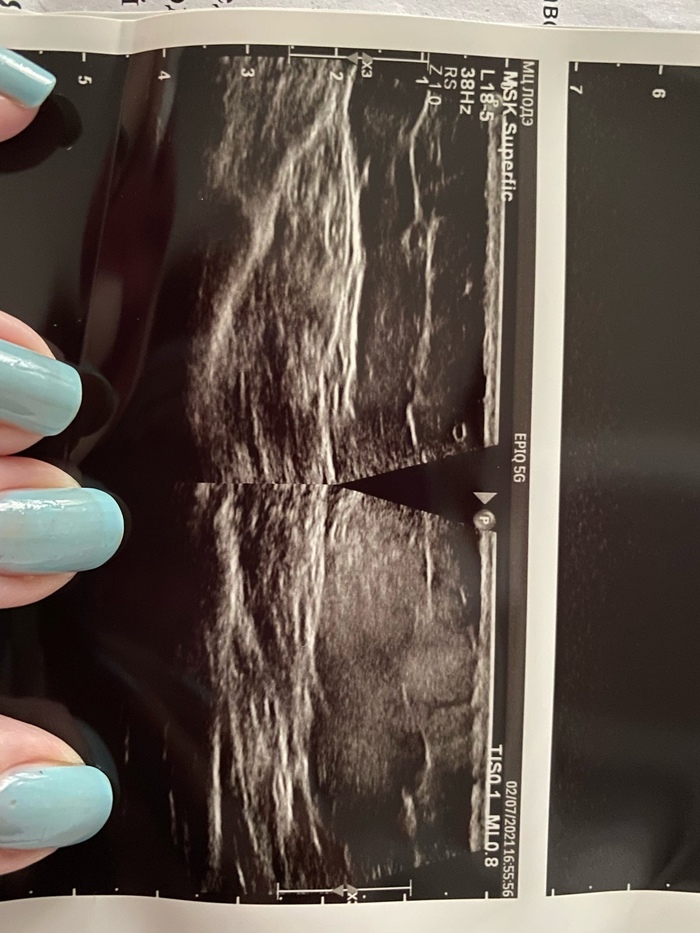

02.07. Проведено УЗИ мягких тканей плеча, подкожная жировая клетчатка утолщена диффузно до 22 мм, на контрлатальной стороне 14 мм, в проекции имеющегося участка гиперемии. Дольчатое строение нарушено, соединительнотканный рисунок нечеткий, размытый, эхогенность повышена, структура неоднородная с участками повышенной эхогенности. При ЦДК усиление кровотока в этой области. Объемные и жидкостные образования не определяются. Фото 2. Слева здоровое плечо, справа больное. Консультация хирурга - продолжать антигистаминные, добавить НПВС (нимесулид), наблюдать. При появлении пульсации или высокой общей температуры записаться еще раз. Фото руки номер 3.Общая температура 37.0